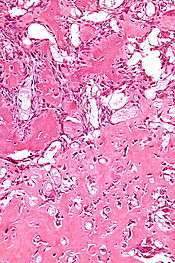

| Micrograph of an osteoblastoma. H&E stain. | |

The etiology of osteoblastoma is unknown. Histologically, osteoblastomas are similar to osteoid osteomas, producing both osteoid and primitive woven bone amidst fibrovascular connective tissue, the difference being that osteoblastoma can grow larger than 2.0 cm in diameter while osteoid osteomas cannot. Although the tumor is usually considered benign, a controversial aggressive variant has been described in the literature, with histologic features similar to those of malignant tumors such as an osteosarcoma.